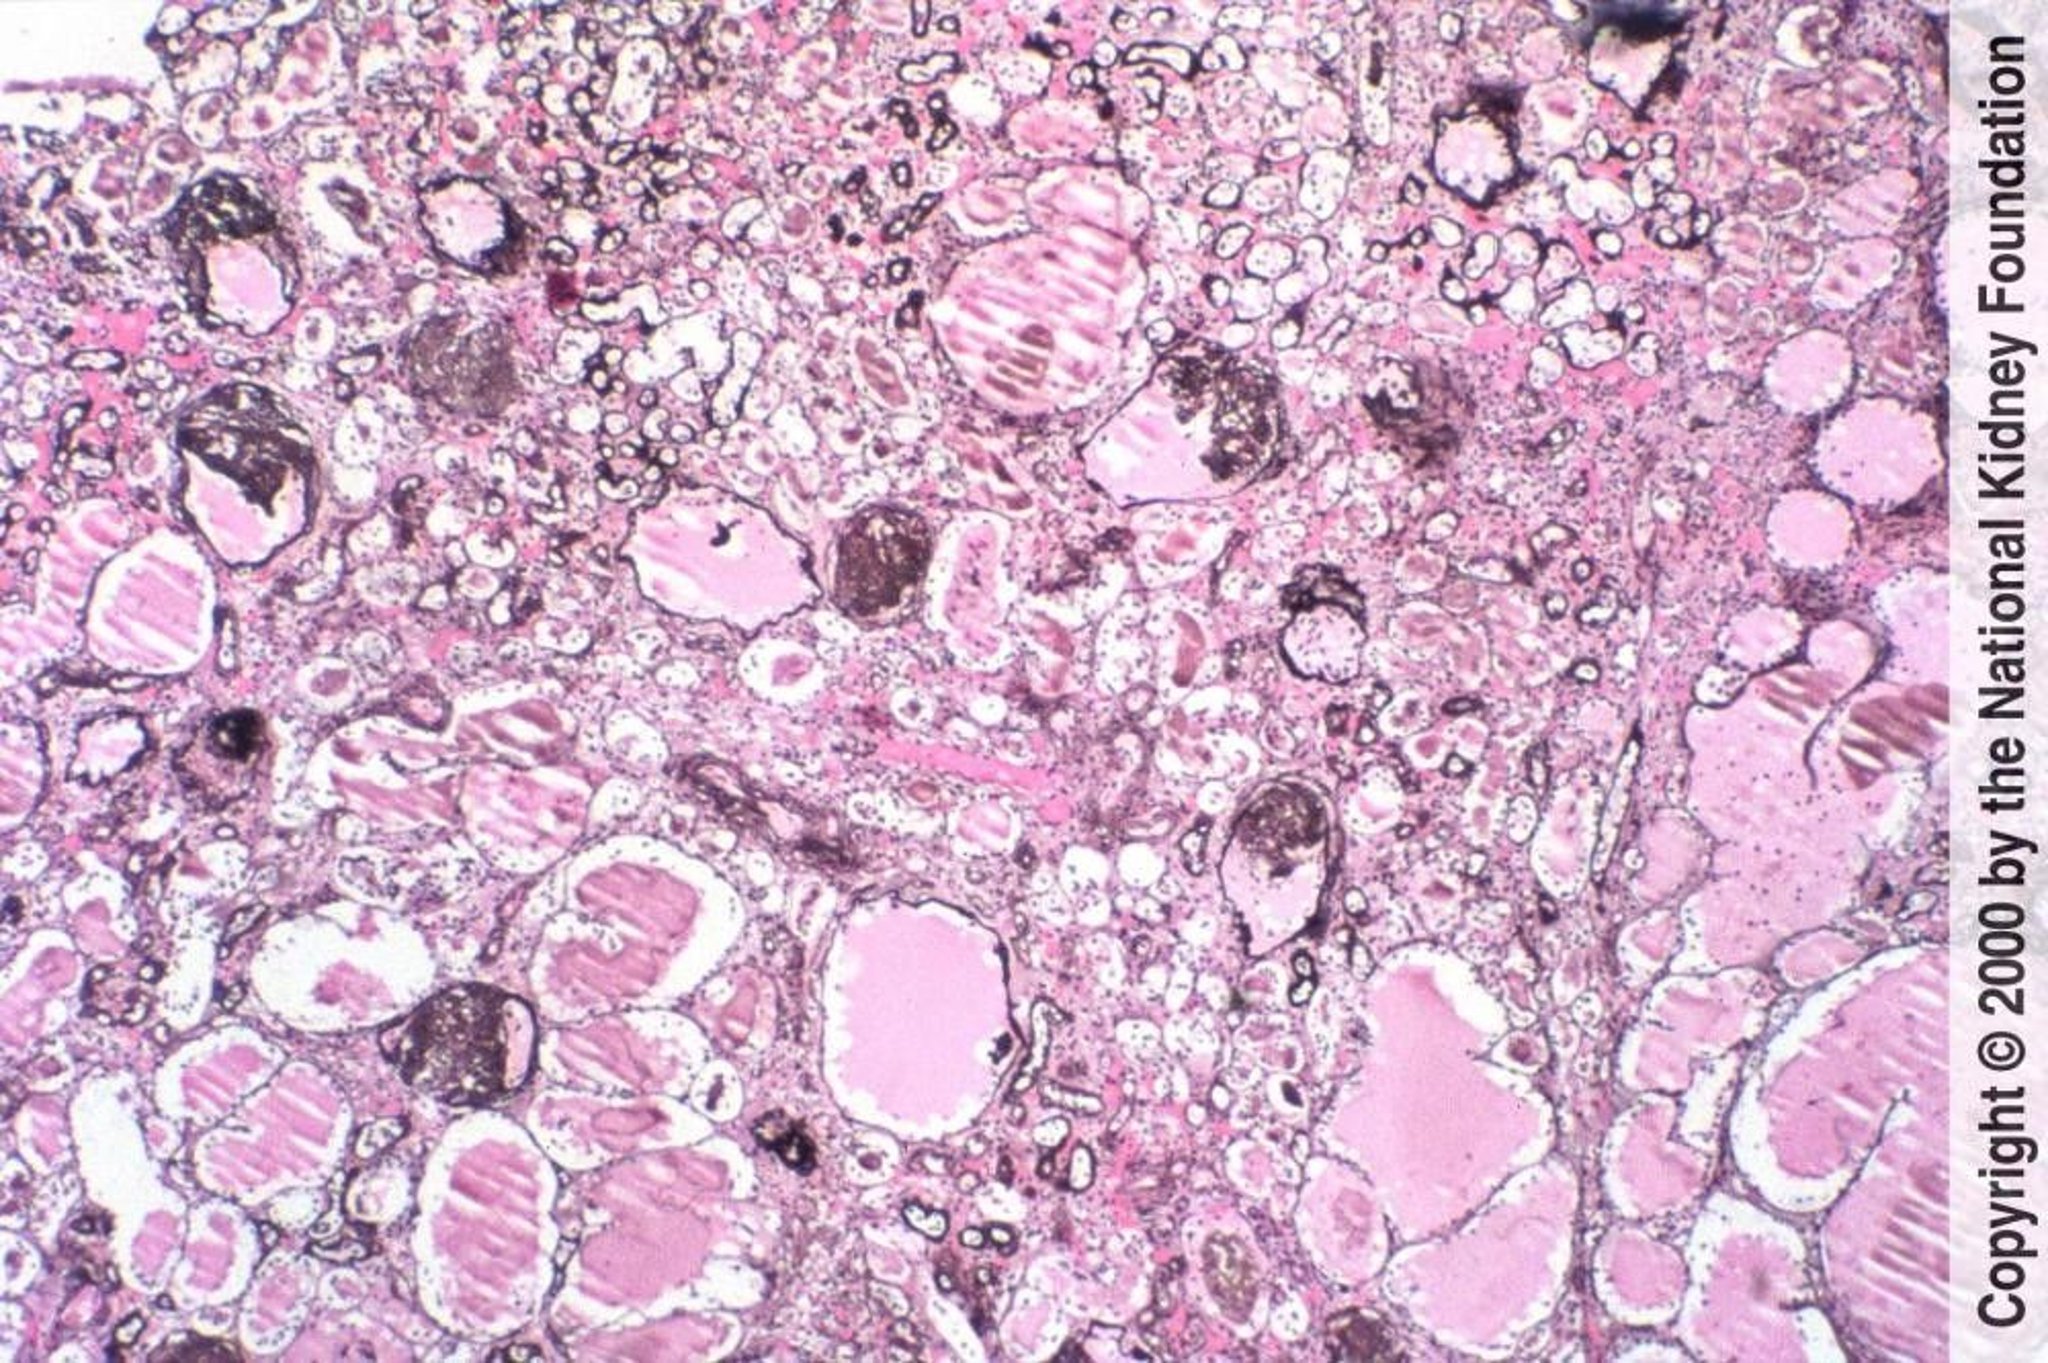

HIV-Associated Nephropathy (Collapsing Glomerulopathy)

Focal segmental glomerulosclerosis with collapse of glomerular tufts and microcystic tubular changes is characteristic of HIV-associated nephropathy (Jones silver stain, ×100).

Image provided by Agnes Fogo, MD, and the American Journal of Kidney Diseases' Atlas of Renal Pathology (see www.ajkd.org).